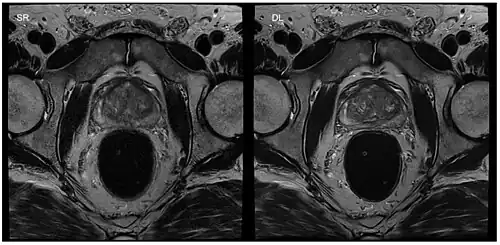

Machine learning

Image reconstruction in RT-MRI benefits from machine learning (ML) or deep learning (DL). A nonlinear kernel, or mapping function, can be developed from the ACS to fill in k-space data and generate the final image.[37] This process as a whole significantly accelerates the MRI process. Image segmentation or identification of lesions can be achieved through machine learning. In deep learning, with a convolutional neural network, the mapping function can be specified by the network. ML and DL improve image resolution as well as imaging speed.[37]